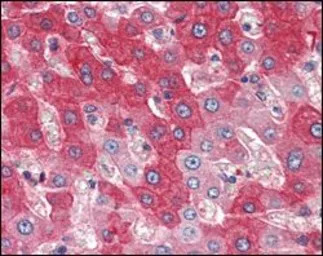

IHC-P analysis of human liver tissue using GTX83291 FGFR4 antibody [4H2B10B2].